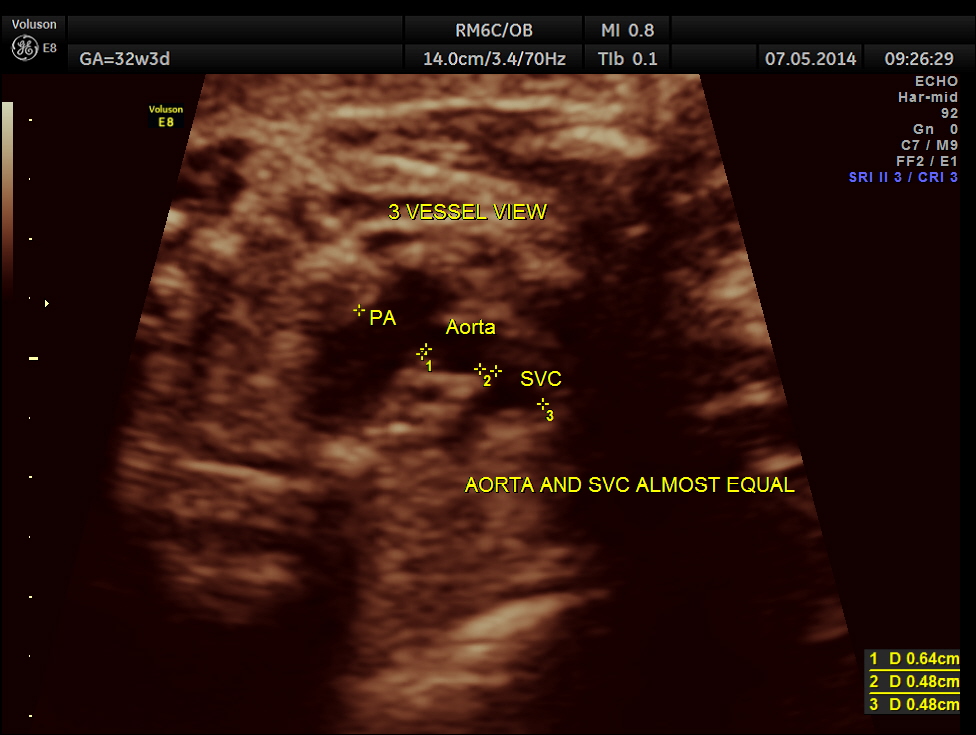

3 vessel view also shows the pulmonary artery to be bigger in size than the aorta.

No definitive pulmonary vein draining into the left atrium could be made out . A common transverse vessel was seen beneath the left atrium . The LA & RA were smaller than the RA. Similarly the Aorta and the aortic arch were smaller than the pulmonary artery and the ductal arch due to the increased flow in the right side.